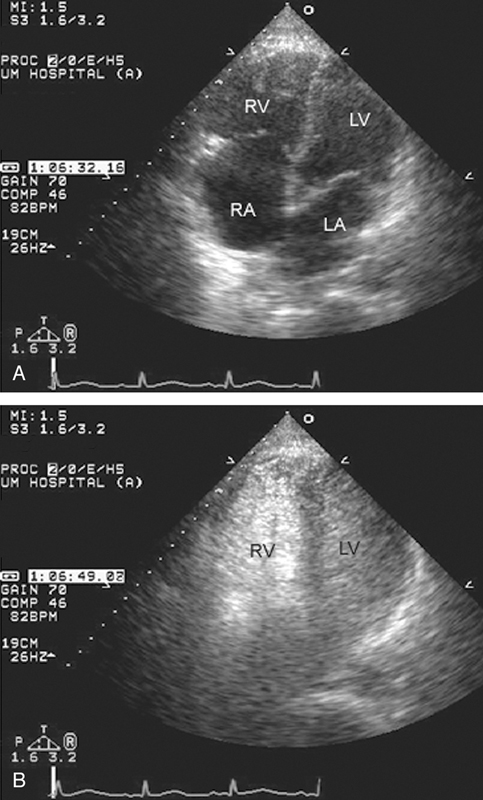

فحوصات تشخيصية لبعض امراض القلب والشرايين التاجية